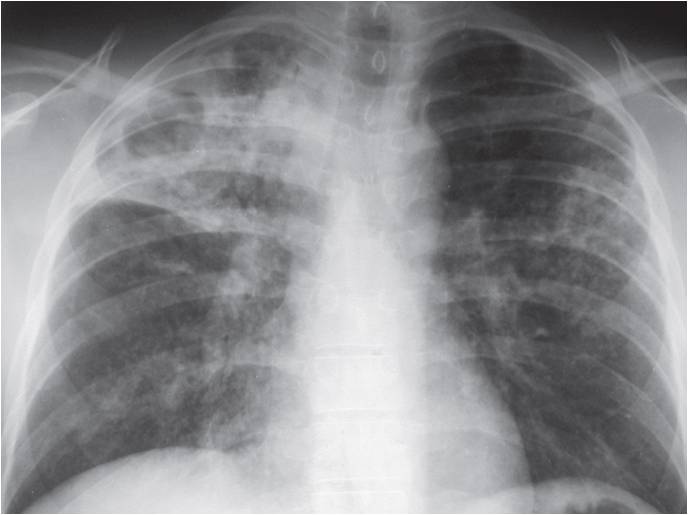

The following are examples of how Active TB may look on CXR:

Mimics any pneumonia; occurs in debilitated pts, when Mtb first enters lung, and innate immune system unable to contain it.